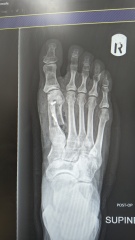

has anyone had bunions and had anything that helped at all? I’ll add a pic below to show what it’s like in terms of severity

Honestly the deviation isn't that severe at first glance so I'm puzzled by the level of pain. Suggests perhaps other foot mechanics issues - my transverse arches both collapsed and I developed bursitis between three metatarsals plus hammer toes both second toes. Wasn't keen on surgery so saw private podiatrist for custom insoles [pricey but worth it] and only wear one type of trainer [New Balance 574 half a size up].